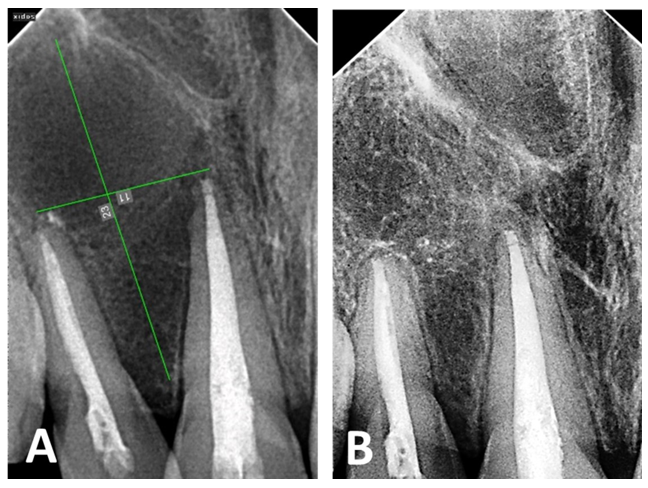

After 24 months, follow-up radiographs showed up-righting of tilted roots and a decrease in radiolucency of the lesion, reflecting healing with new bone formation. The severe displacement was corrected, and the patient no longer required orthodontic treatment (Figure 5).

Figure 5 The post-operative radiograph (A) shows the extension of the periapical lesion and tilted roots, and the radiograph after 24 months (B) shows the healing of the periapical lesion and straightening of the tilted roots.